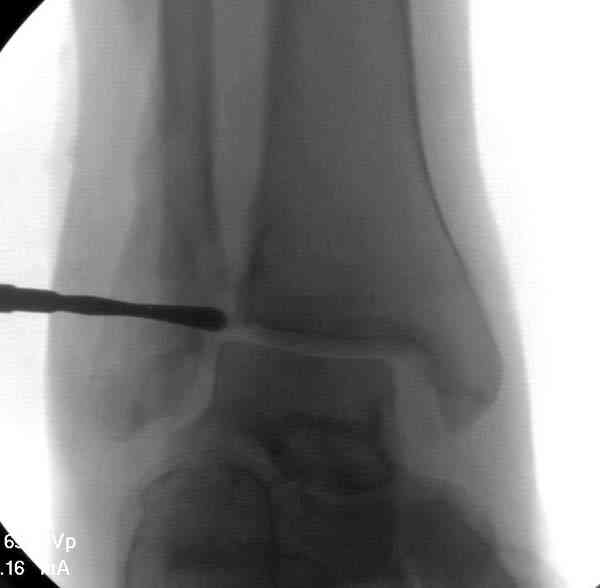

Мне кажется есть все основания попытаться сделать остеосинтез. Боль вследствие нестабильности. Нестабильность вследствие неанатомичного положения дистального отломка малоберцовой кости. Через 1,5 вполне возможно разобщить, репонировать и фиксировать длинный косой перелом наружной лодыжки. Вероятно, одновременно придется делать медиальный доступ для мобилизации внутренней лодыжки. Мы оперируем таких пациентов, функциональные (объем движений) результаты конечно хуже по сравнению с теми кого оперируем в первые 5-10 дней, но вполне удовлетворительные.

Согласен, на предоставленных рентгенограммах все основания для проведения открытого остеосинтеза.

сроки действительно небольшие, но если мы его и возьмем, то пройдет еще минимум неделя, кроме того смущает впечатление сращения н/лодыжки, похоже, что придется не разобщать,а остеотомировать, формирование оссификатов в полости сустава с медиальной стороны, да и сам пациент 1,5 месяца по поводу своей травмы сильно не напрягался